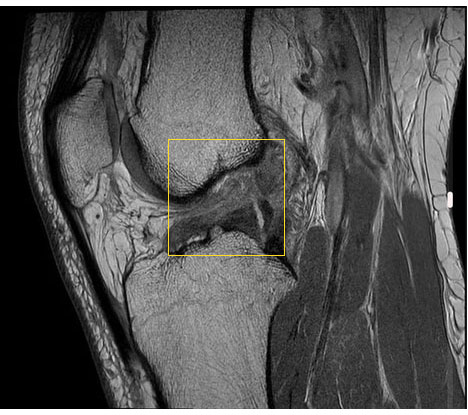

Untersuchung des Kreuzbandrisses mit Kernspintomografie (MRT)

Die im Röntgen oder durch klinische Untersuchungen nicht eindeutig feststellbaren Kreuzbandrisse kann eine MRT (Magnetresonanztomografie) viel besser darstellen.

Schwierig wird die Diagnose mittels MRT erst, wenn das Kreuzband nicht ganz gerissen ist, sondern nur gedehnt ist bzw. eine Teilruptur erlitten hat.

Teilrupturen des Kreuzbandes kann die Bildgebung nicht sicher darstellen. Man erkennt nur schwer, in welchen Anteilen das Kreuzband noch intakt ist. In diesen Fällen muss der Kniespezialist mit viel Erfahrung die Überbeweglichkeit des Kniegelenks im Vergleich zum anderen Knie überprüfen (Schubladentest).

Ein kompletter Bandabriss verläuft häufig symptomarm. Teilrupturen sind von kompletten Abrissen in der klinischen Untersuchung schwer zu unterscheiden. Ergebnisse von Röntgen- sowie Kernspinuntersuchungen ergeben nicht selten fälschlicherweise negative Befunde. Man sieht also im Bild ein scheinbar intaktes Kreuzband, dessen innere Struktur – und damit auch seine Funktion – deutlich zerstört ist. Bei diesen falsch-negativen Befunden scheint das Kreuzband anatomisch intakt, obwohl es in Wirklichkeit keine Funktion mehr ausübt.

Das Kreuzband besteht aus vielen Einzelfasern, die mit einer Hüllstruktur umgeben sind – ähnlich wie bei einem ummantelten Telefonkabel. Die Fasern reißen häufig im Inneren, während die Hülle noch intakt ist. Bleibt die Umhüllung unversehrt, misslingt der Nachweis des Kreuzbandrisses im Kernspin, weil die Struktur äußerlich intakt zu sein scheint.

Werden die Fasern komplett durchtrennt, führt dies in Abwesenheit von starken Begleitverletzungen zu einer Schwellung, die häufig nach 1–2 Tagen wieder abklingt.

Danach kann das Knie mit Kreuzbandriss über Jahre relativ symptomfrei, aber funktionell instabil sein. Daher werden viele Kreuzbandrisse erst Monate oder sogar Jahre nach der Ruptur diagnostiziert.

Erst wenn sekundäre Symptome wie Meniskusrisse und Knorpelschäden auftreten, wird deren Ursache – oftmals arthroskopisch – erkannt. Es handelt sich dabei häufig um einen Jahre zurückliegenden Kreuzbandriss.